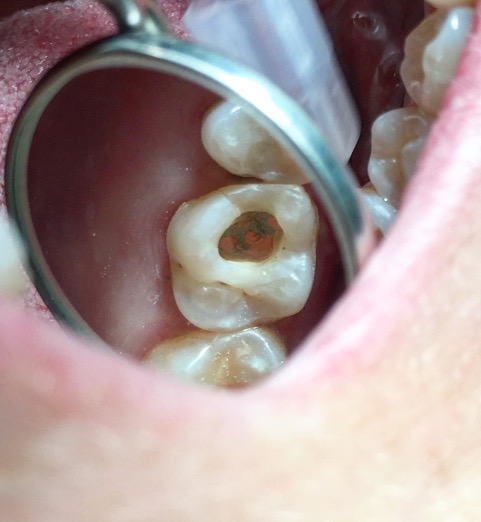

Una corretta terapia canalare con un perfetto sigillo a livello degli apici delle radici è fondamentale. I denti devitalizzati impropriamente possono creare ulteriori problemi che poi andranno a ripercuotersi sulle cure effettuate successivamente come le ricostruzioni e le corone protesiche con conseguente fallimento del piano terapeutico.

Capita spesso di incontrare denti già devitalizzati in maniera impropria che necessitano, seppur asintomatici, di essere ritrattati per evitare che i granulomi infetti visibili radiograficamente si evolvano riassorbendo tutto l’osso sottostante.